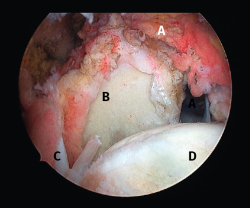

Figura 3. Rotura del manguito rotador en forma de L. A: tendón infraespinoso; B: tendón supraespinoso; C: glena; D: cabeza humeral.

Figura 8. Rotura de tipo C4. A: rotura masiva del tendón supraespinoso con presencia de degeneración grasa; B: glena; C: rotura masiva del tendón infraespinoso; D: cabeza humeral.